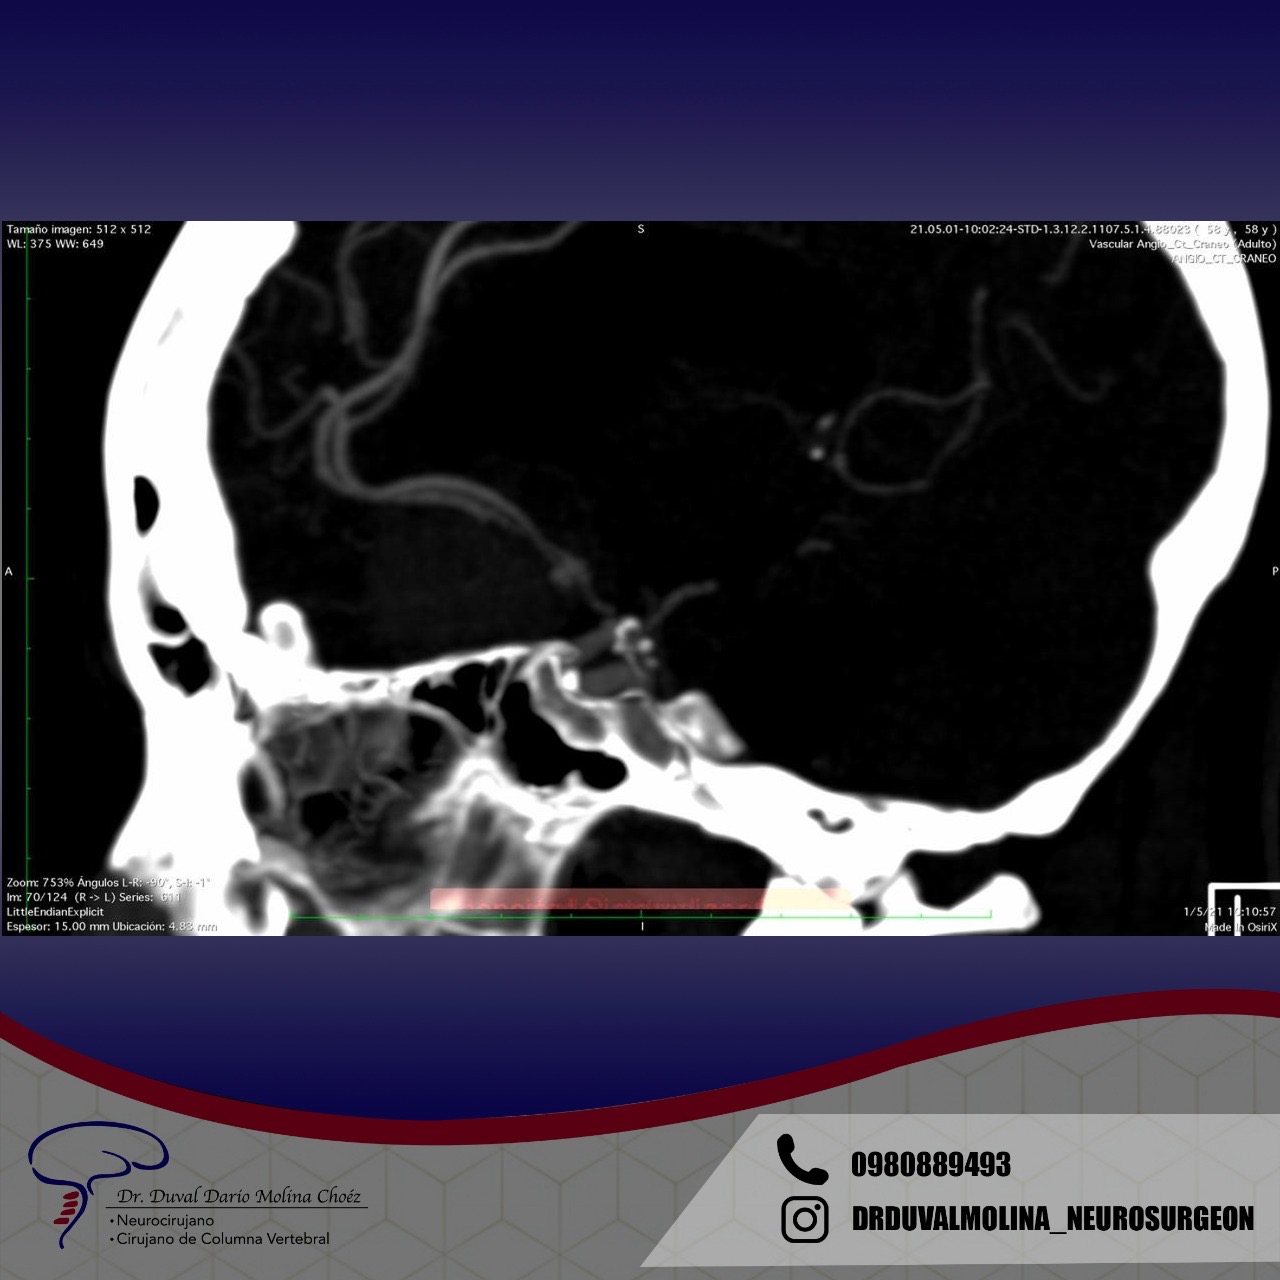

Recurrent aneurysm seen near clips

3D brain angiography showing an aneurysm